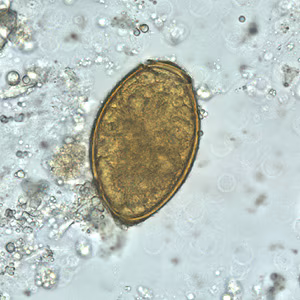

Eggs of Paragonimus spp. in unstained wet mounts.

Diagnosis is based on microscopic demonstration of eggs in stool or sputum, but these are not present until 2 to 3 months after infection. (Eggs are also occasionally encountered in effusion fluid or biopsy material.) Concentration techniques may be necessary in patients with light infections. Biopsy may allow diagnostic confirmation and species identification when an adult or developing fluke is recovered.